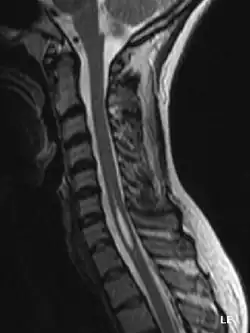

Jamistość rdzenia (łac. syringomielia, ang. syringomyelia) – przewlekła, dość rzadka choroba rdzenia kręgowego, a czasem także pnia mózgu (jamistość opuszki, syringobulbia) charakteryzująca się powstawaniem cewkowatych jam w rdzeniu kręgowym, zwykle w odcinku szyjnym, z tendencją do rozszerzania się na pozostałe odcinki. Choroba rozpoczyna się zwykle w trzeciej lub czwartej dekadzie życia i ma charakter powoli postępujący. Najczęstsze objawy to tzw. rozszczepienne zaburzenia czucia, osłabienie, często asymetryczne kończyn górnych z zanikami mięśniowymi, może dołączyć się także osłabienie kończyn dolnych i zaburzenia chodzenia, a także (w późnym okresie choroby) zaburzenia zwieraczy. Przyczyna choroby pozostaje niejasna, chociaż zauważalne jest współistnienie jej w dwóch trzecich przypadków z zespołem Arnolda-Chiariego. Leczenie jamistości rdzenia dotyczy przypadków z powiększającymi się jamami syringomielicznymi i polega na neurochirurgicznym drenażu jamy.

Innym obszarem ciągłych poszukiwań jest diagnostyka. Jak dotąd, MRI pozwoliło oglądać naukowcom stan kręgosłupa, włączając w to syringomielię, nawet przed wystąpieniem objawów. Nowa technologia, zwana dynamicznym MRI, pozwala badaczom wyświetlić płyn rdzeniowo-mózgowy pulsujący w syrinx. Tomografia komputerowa pozwala lekarzom zaobserwować nieprawidłowości w mózgu, a inne testy diagnostyczne również rozwinęły się z możliwością nowych, nietoksycznych barwników kontrastowych.